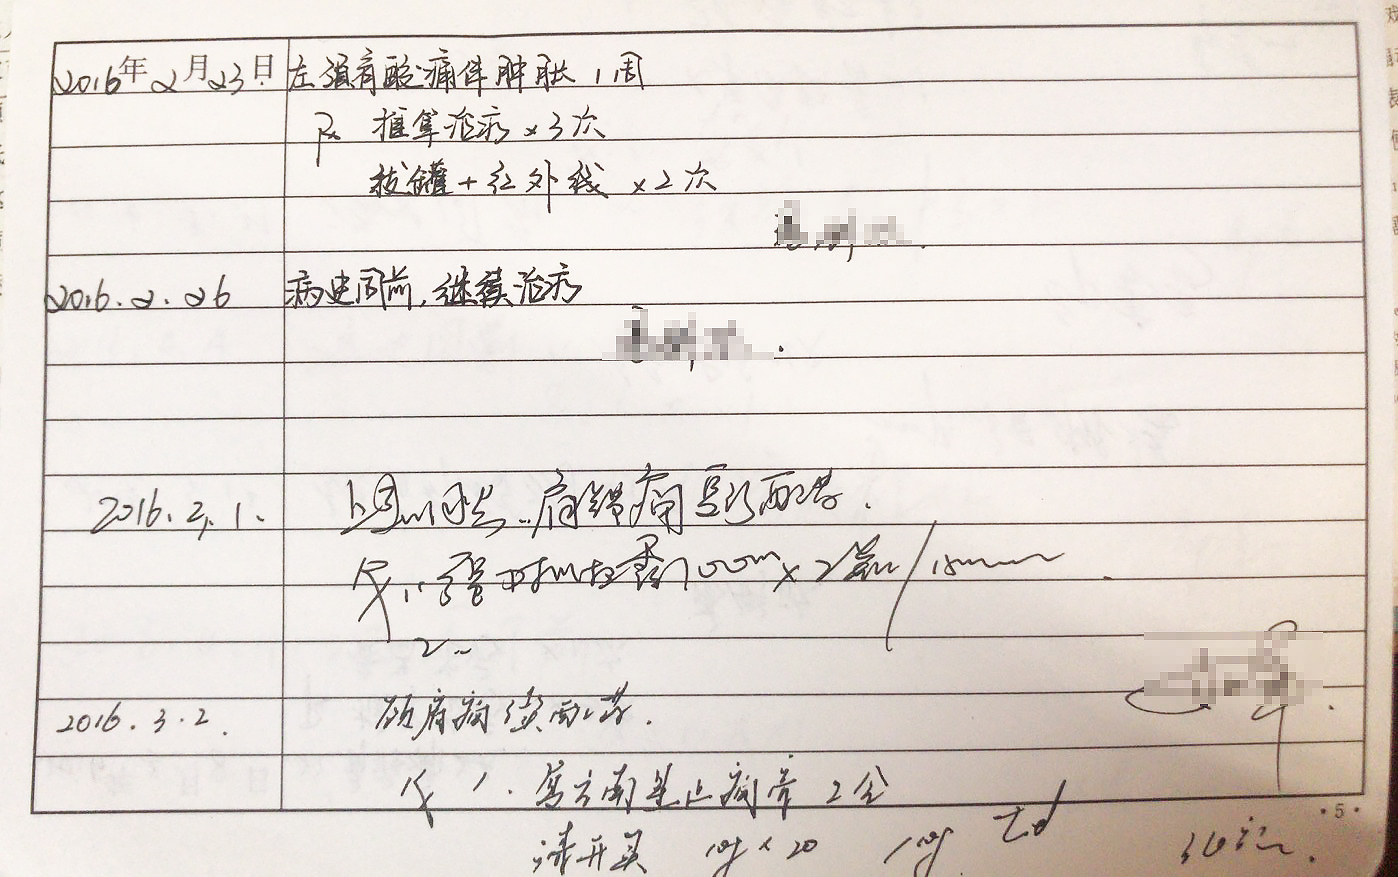

阶级会在一个人的身上留下最深刻的烙印。颈椎病、腰椎间盘突出、腕管综合征等,这一切都向我们表明,实时通讯的自动化社会改造了我们的身体。同样地,如果你的键盘用得足够得久,总有几个键帽会被敲打到面目模糊。键盘作为一个外置化的器官,为我们呈现了在这个技术时代肉眼可见的器官损耗。

现在,我们邀请每一位赛博格,分享你作为赛博格的受损器官图像,我们将以此作为元数据,建立起一个文献档案库。颈椎也好,键盘也罢,都是我们被困在系统里的在场证明。